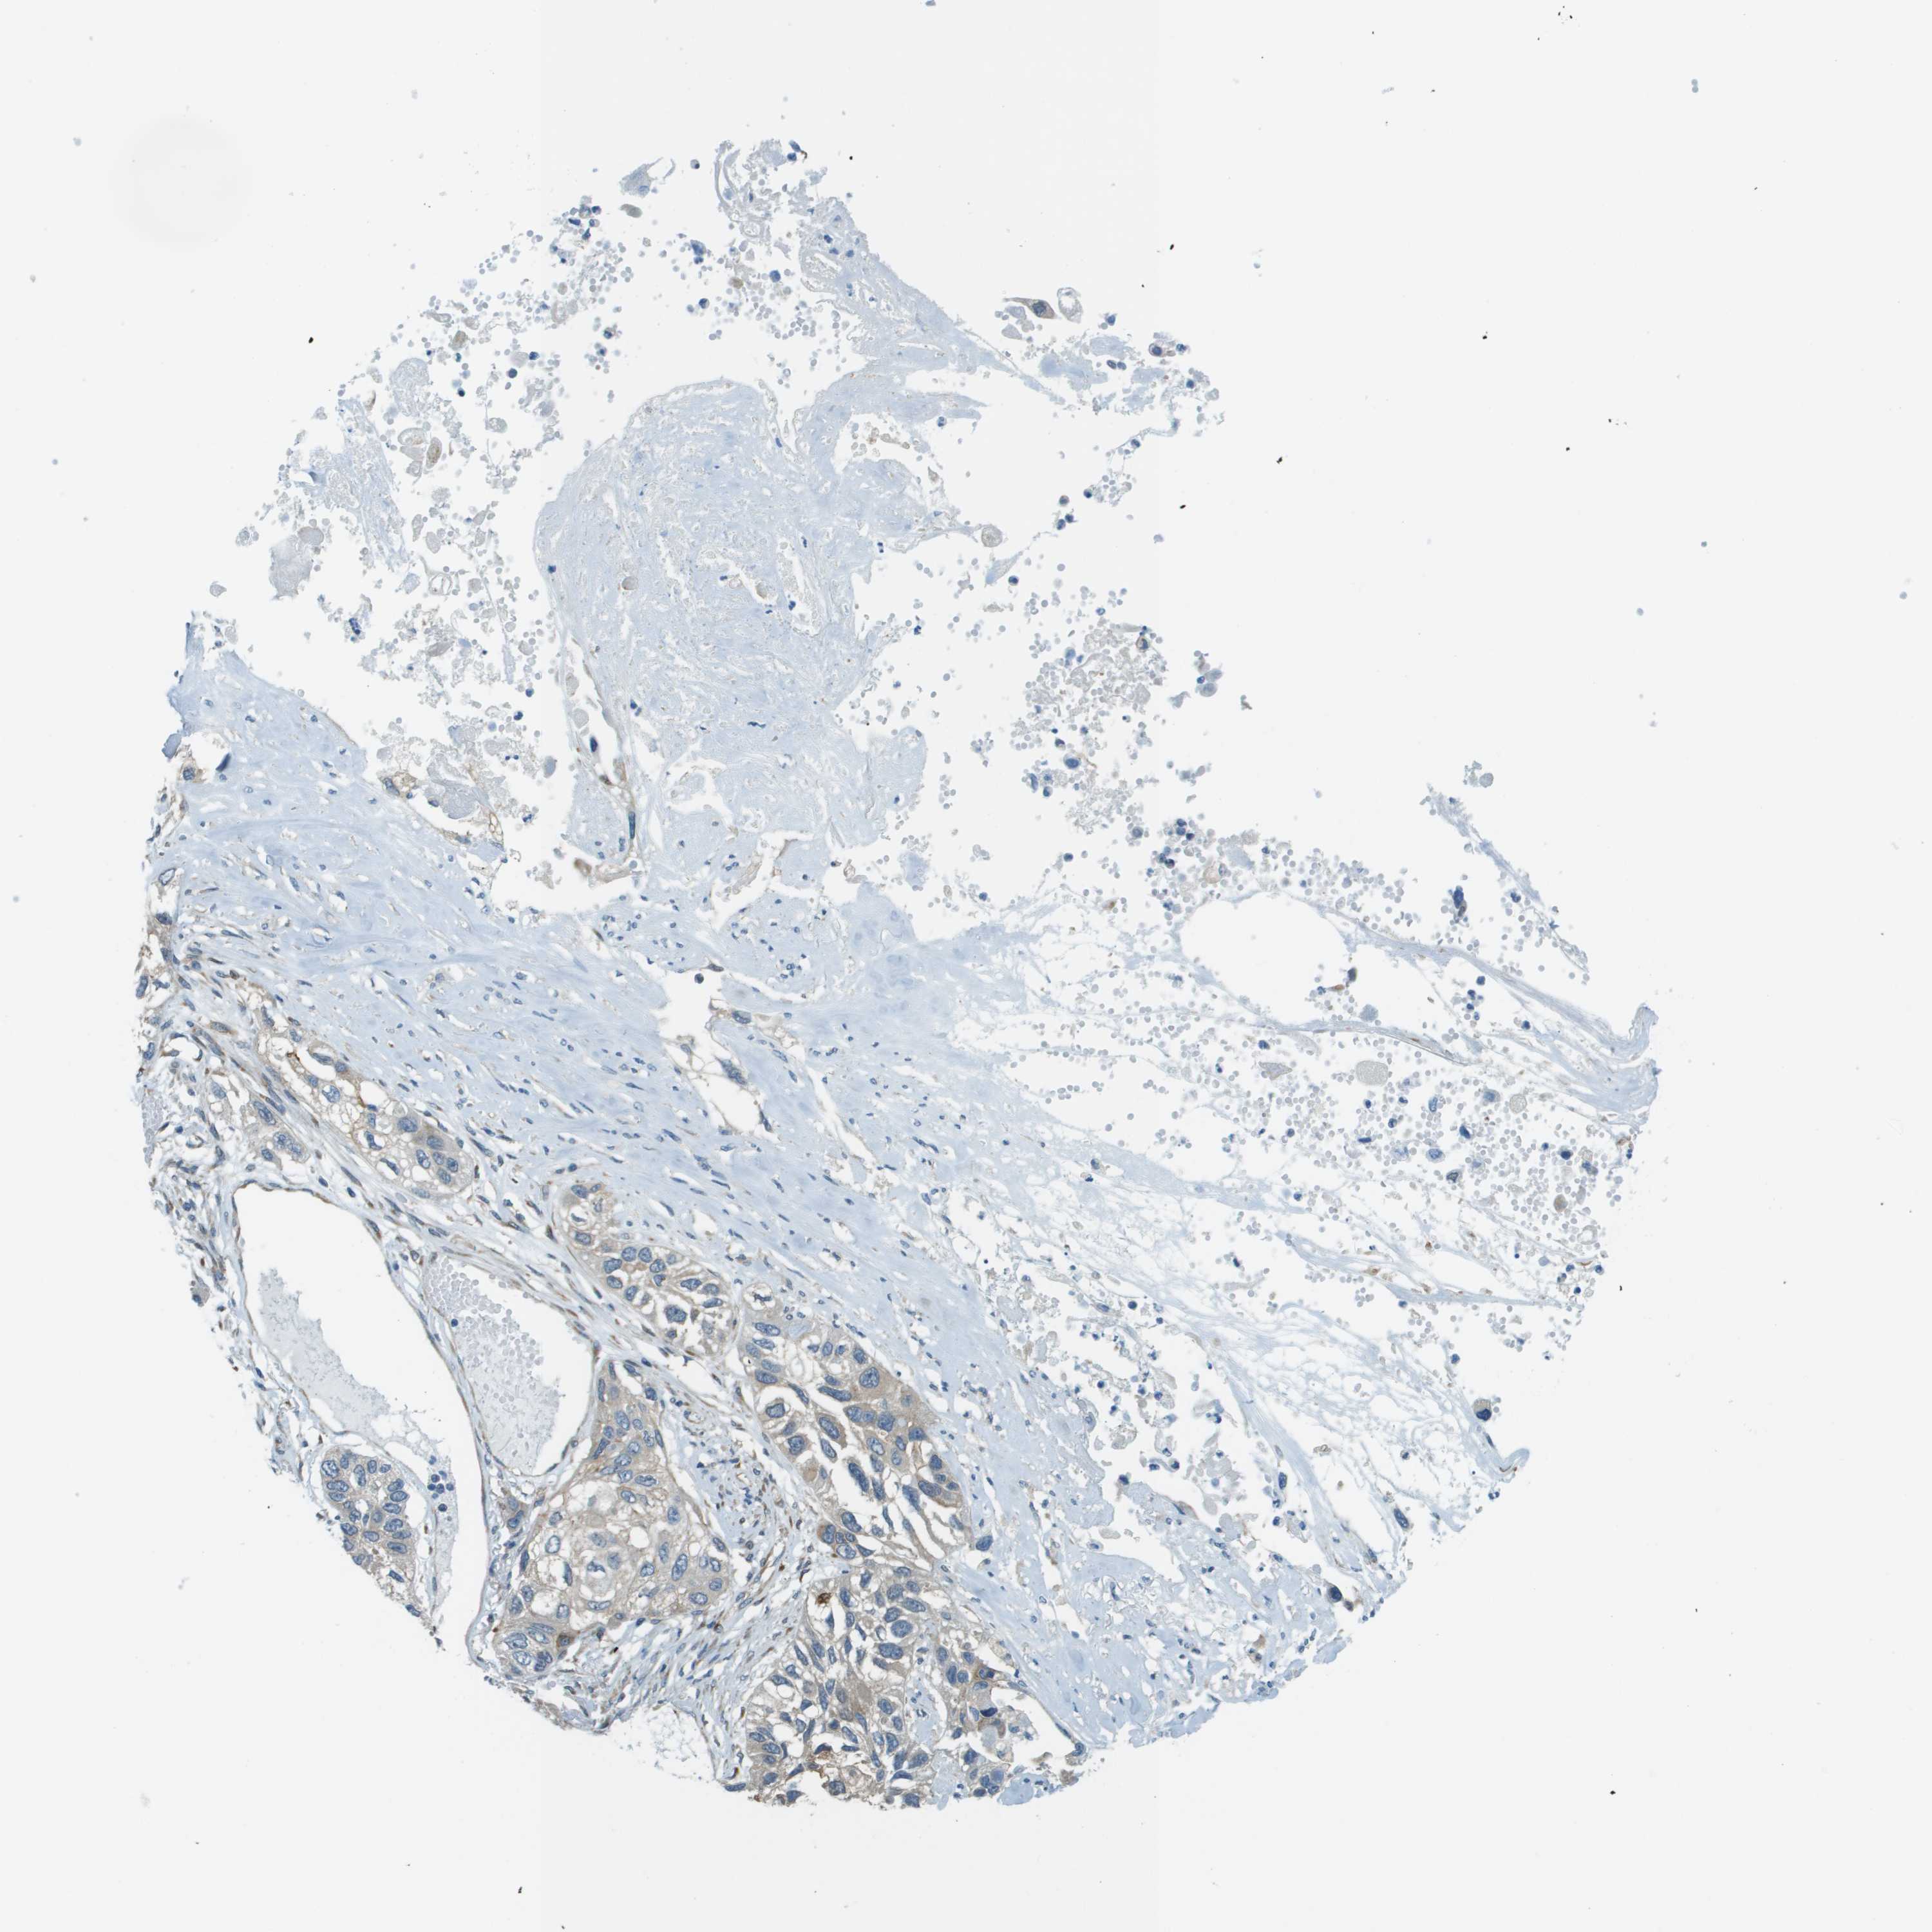

CANCER LUNG CANCER Show tissue menu

ACBD3 is potential prognostic, high expression is unfavorable in Lung Adenocarcinoma (validation)